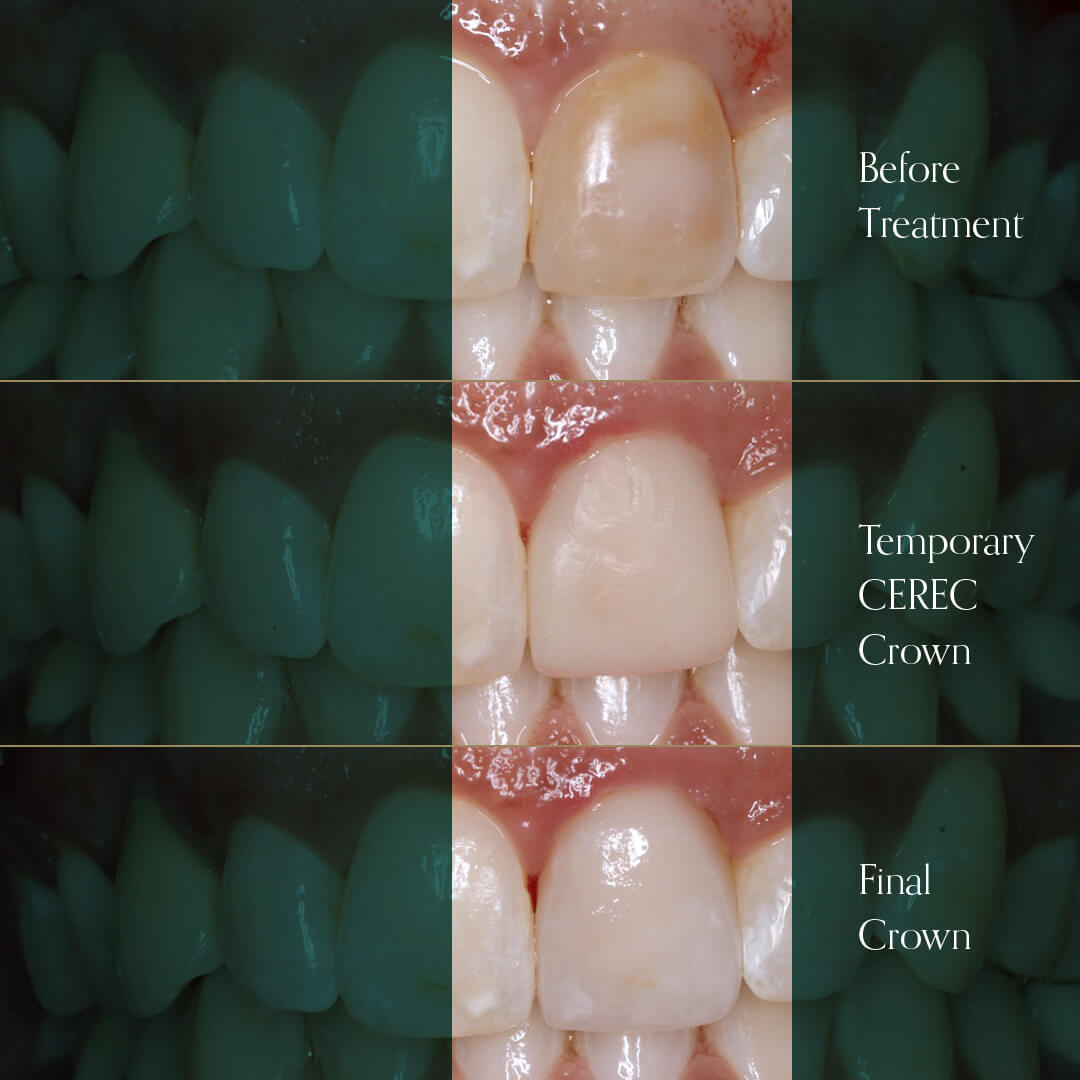

- Broken, chipped, worn out or damaged teeth

- Can also be used to mask discoloured teeth or straighten teeth using veneers

Our cosmetic dentists use their expertise and creative skills to produce quality restorations for a smile that is healthy, natural looking, and beautiful.